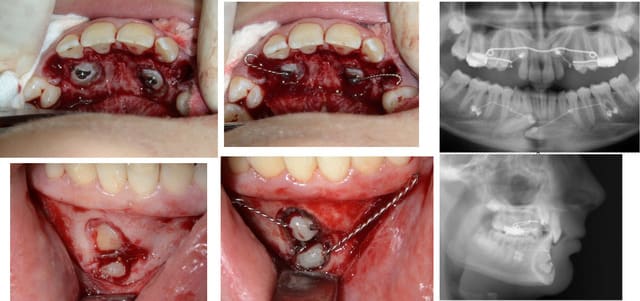

jeune fille pour une désinclusion de 23, 10 ans sur la carte vitale, dentition en avance pour son age

Sinon c'est un odontome composé ton truc = tumeur odontogène

Sans doute hormis les deux surnumerairaires tout était dans un sac, mais comme, je ne m'y attendais pas je ne peux pas dire s'il était fermé ou ouvert.

Pour ce cas collage de l'arcade 15 jours avant

sur la photo 2 on distingue les 2 germes l'un au dessus de l'autre (eh non pxav je n'y arrive tjrs pas pour les photos)

trajet , "excision" sinon cela saigne un peu trop, dégagement de la couronne a minima,collage pose de la chainette en traction, régularisation des cretes, sutures

30 minutes entre l'entrée et la sortie de la patiente